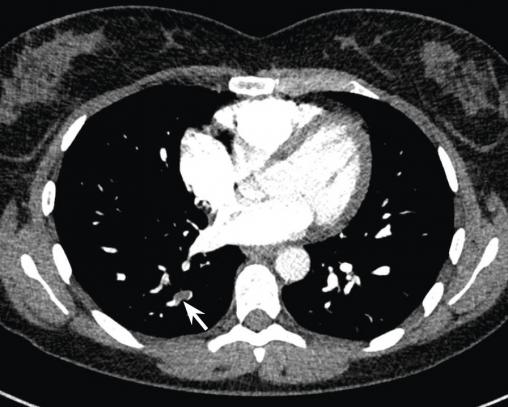

Une semaine après l’arrêt de l’aspirine, une dyspnée au moindre effort réapparaît. Les douleurs précordiales persistent mais sont moins intenses. Les D-dimères sont à 804 ng/mL, la CRP est à 11 mg/L et la troponine est négative. Un angioscanner pulmonaire réalisé en urgence montre une embolie pulmonaire sous-segmentaire postéro-basale droite, non compliquée.

Une lame d’épanchement péricardique est visible. La patiente est mise sous anticoagulant oral direct.